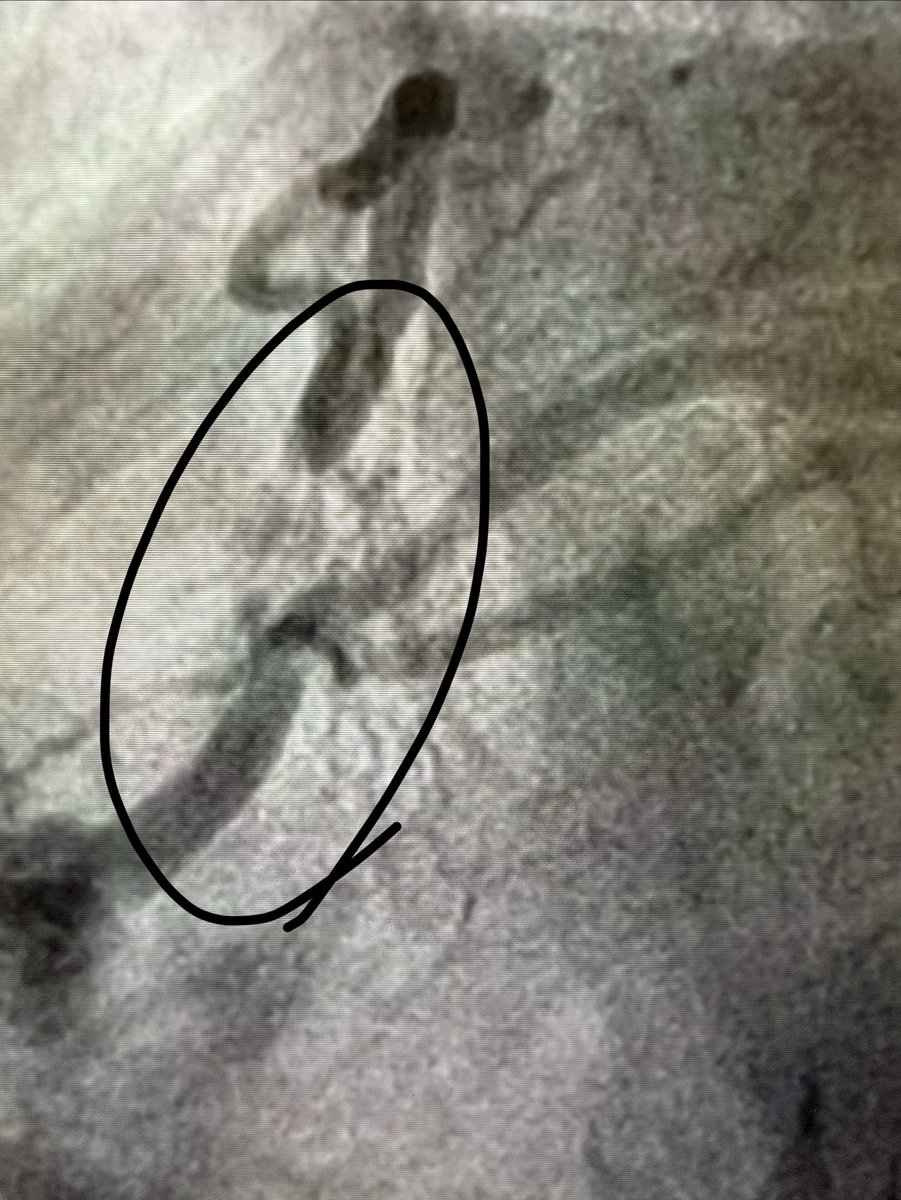

When your transseptal LV angiovac thrombectomy does not go as expected… but you are ready with the @ONOCORvascular in the ascending aorta 🙃

ŌNŌ helps again…

Great save by @CraigBasman and the team at Hackensack University Medical Center.

English

A nice save by the team at HUMC with Ono Retrieval..

@ONOCORvascular ,

Every high volume center should have this device on their shelf!

@vandanMD @PWengrofskyMD @SHYoonMD

#mitraclip

#structuralheart